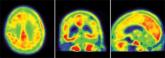

In vivo tau imaging confirms patient’s Alzheimer’s diagnosis

- Author:

- Michele G. Sullivan

Publish date: July 17, 2013